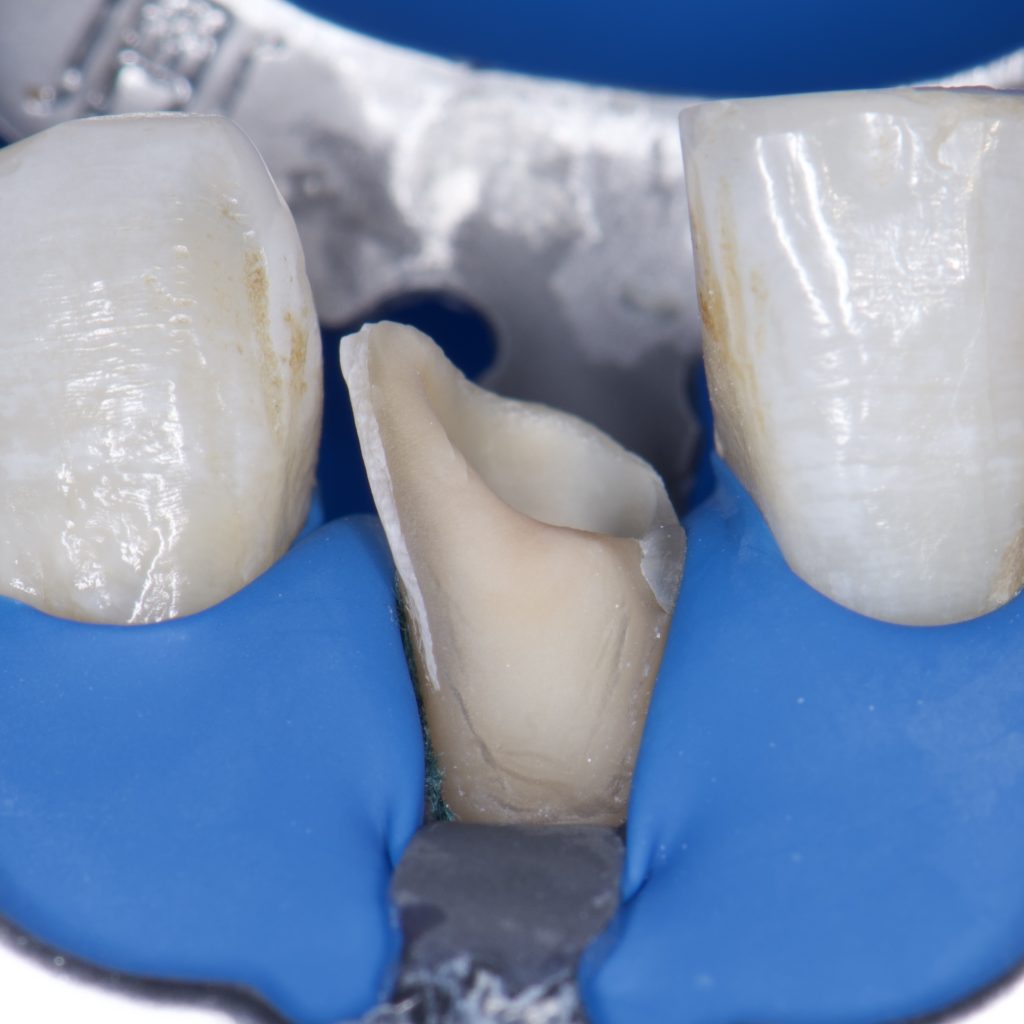

-Isolation with rubber dam

– SE clearfil bond

– Ribbond

– Direct composite restoration, layering technique